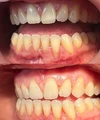

نزيف اللثة

أمراض الأسنان واللثة